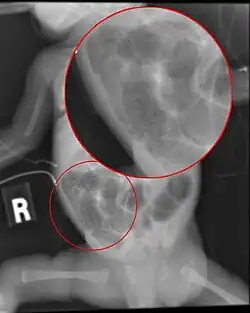

Diagnosis is usually suspected clinically, but often requires the aid of diagnostic imaging, most commonly radiography, which can show the intestines and may show areas with dead tissue or a bowel perforation.[18] Specific radiographic signs of NEC are associated with specific Bell's stages of the disease:[19]

- Specific radiologic signs (pneumatosis intestinalis or portal venous gas)

- Severe radiologic signs (pneumoperitoneum)

Ultrasonography has proven to be useful, as it may detect signs and complications of NEC before they are evident on radiographs, specifically in cases that involve a paucity of bowel gas, a gasless abdomen, or a sentinel loop.[21] Diagnosis is ultimately made in 5–10% of very-low-birth-weight infants (<1,500g).[22]

-

Esophagus, stomach and intestines of affected infant showing intestinal necrosis, pneumatosis intestinalis, and intestinal perforation (arrow) (autopsy specimen) -

Close-up of intestine showing extensive necrosis (autopsy specimen)